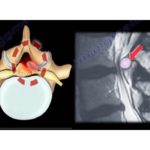

Selective Nerve Root Blocks in Spine Surgery

Courtesy: Rishi Mugesh Kanna, Consultant Spine Surgeon, Ganga Hospital, Coimbatore, India Spinal Injections Spinal injections are defined as injections performed in and around the vertebral column, spinal cord, and nerve roots. They may involve one or more of the following agents: Local anesthetics for diagnostic nerve blocks Steroids for epidural steroid injections Contrast dye for […]